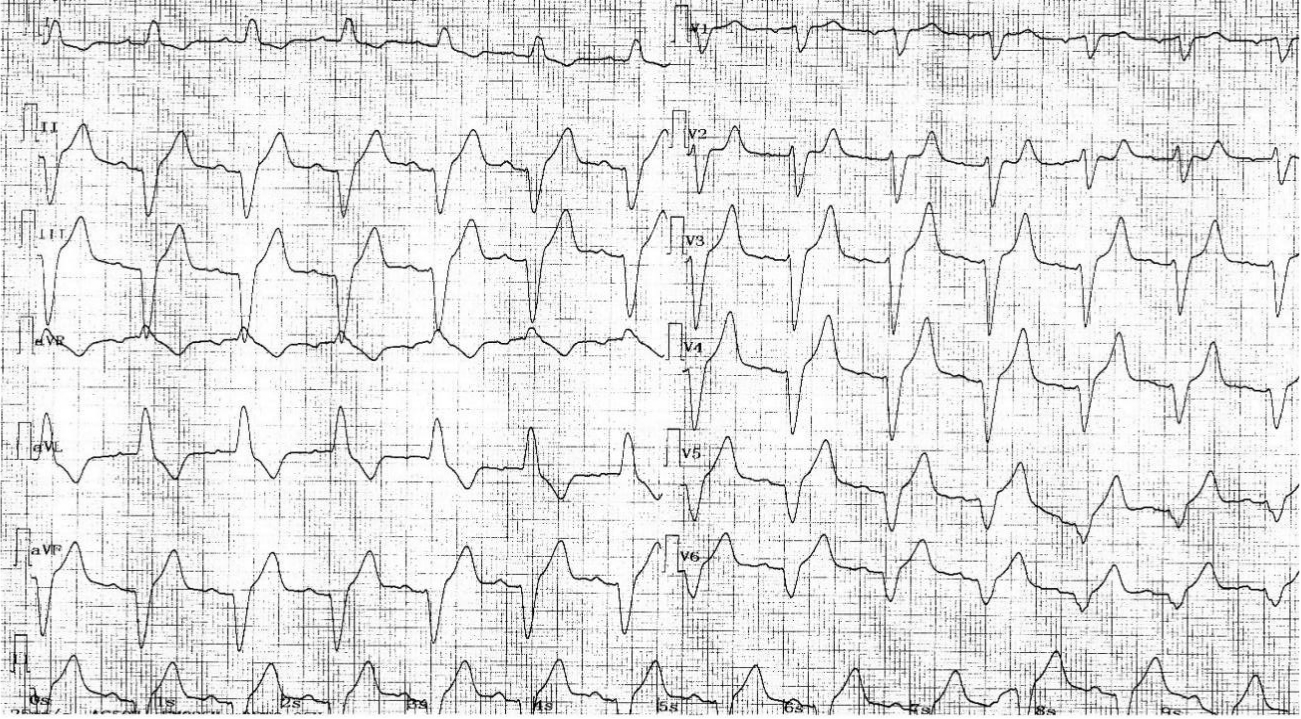

患者術前心電圖改變:Ⅲ--AVB

患者術後心電圖改變:雙腔起搏器 VDD起搏模式